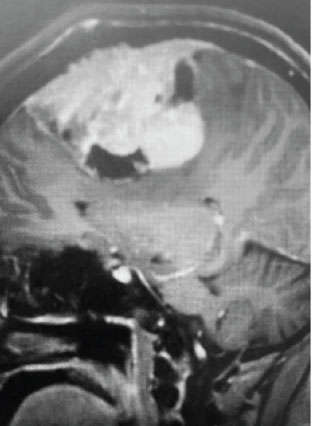

Fig 2. B) Post-operative, post-contrast, coronal MRI.

Treatment: Given the size and location of this tumor, the best treatment was surgical removal. Surgery was performed by Dr. Michael Brisman. A craniotomy exposed the tumor along the convexity as well as the superior sagittal sinus. The tumor was removed, as was the involved convexity dura and the affected segment of the sagittal sinus. Removed dura and skull were replaced with duraplasty (with artificial dura) and a titanium mesh cranioplasty.

Outcome: The patient did very well and made a full recovery.